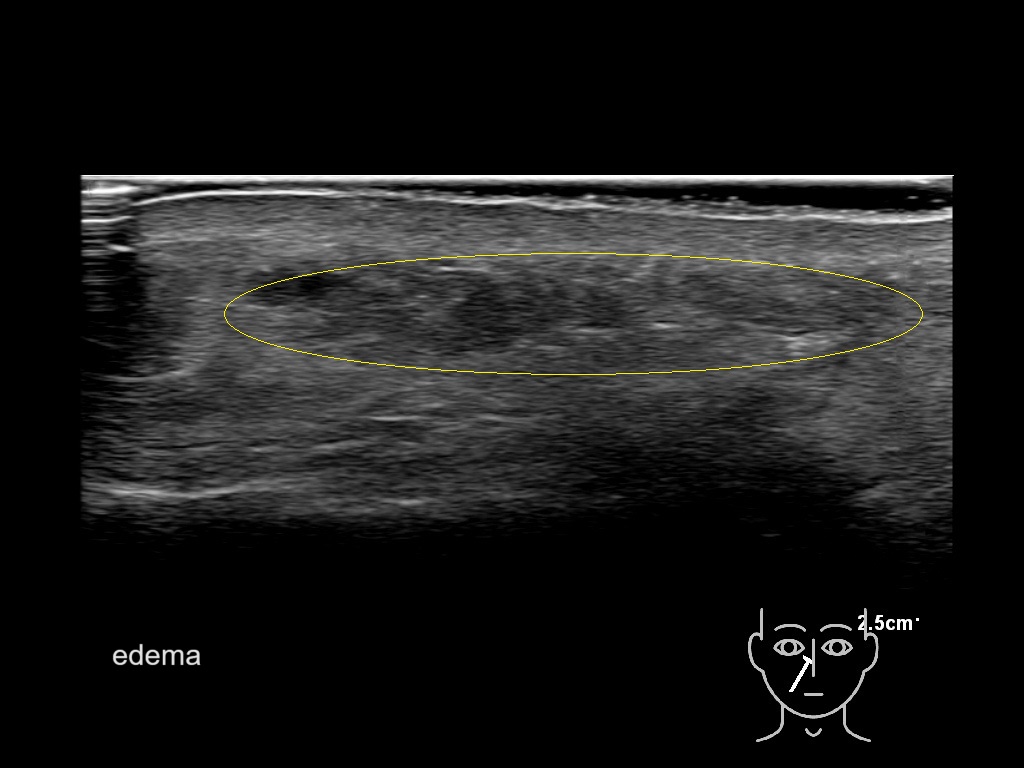

With ultrasound signs of inflammation can be visualized. Edema can be seen as a hyperechoic appearance of the subcutaneous fat, sometimes separated by hypoechoic fluid filled area’s, known as cobblestone appearance. Increased vascularization (hypervascularity) can be seen on colour Doppler. An abscess will appear as a fluid collection appearing as an irregular hypoechoic area with heterogeneous internal echoes and a thickened wall. Posterior acoustic enhancement can be present, and there is vascularity around but not within the mass. Under ultrasound guidance, abscesses can be managed by needle aspirations (18G) under antibiotic cover.

Study the first image to recognize the different layers. If you are sure about the layers, swipe to the second image to view the answer (if applicable).